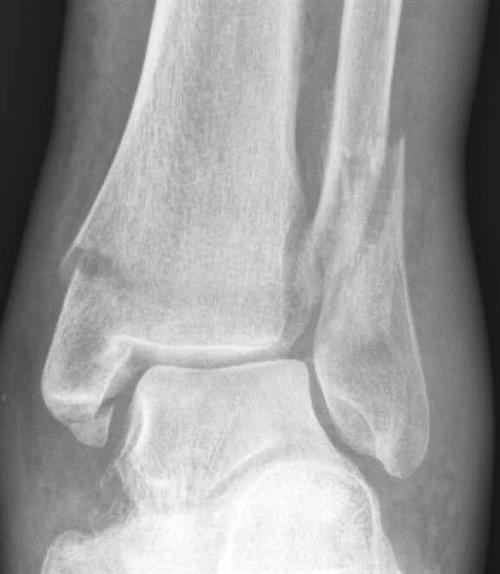

相关图片